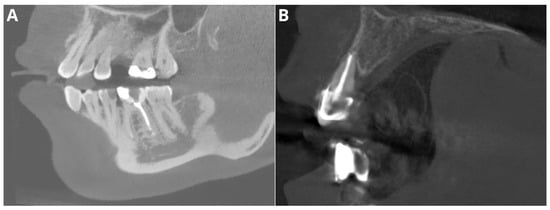

- Probability of filling

- Adequate obturation

- Adequate density

- Overfilling

- Voids in filling

- Short filling

- Probability of filling—evaluation of the presence of radiopaque material within the tooth canals.

- Adequate obturation—assessment of the extent of the filling material up to the apex of the root, verification of material density and consistency through the canal.

- Adequate density—evaluation of the radiopacity and homogeneity of the filling material and identification of areas with lower density indicating voids or inadequate filling.

- Overfilling—examination of any filling material extending beyond the apex of the tooth.

- Voids in filling—identification of radiolucent areas within the filling that indicate the presence of voids.

- Short filling—assessment of the extent of the filling material if it falls short of the tooth apex.